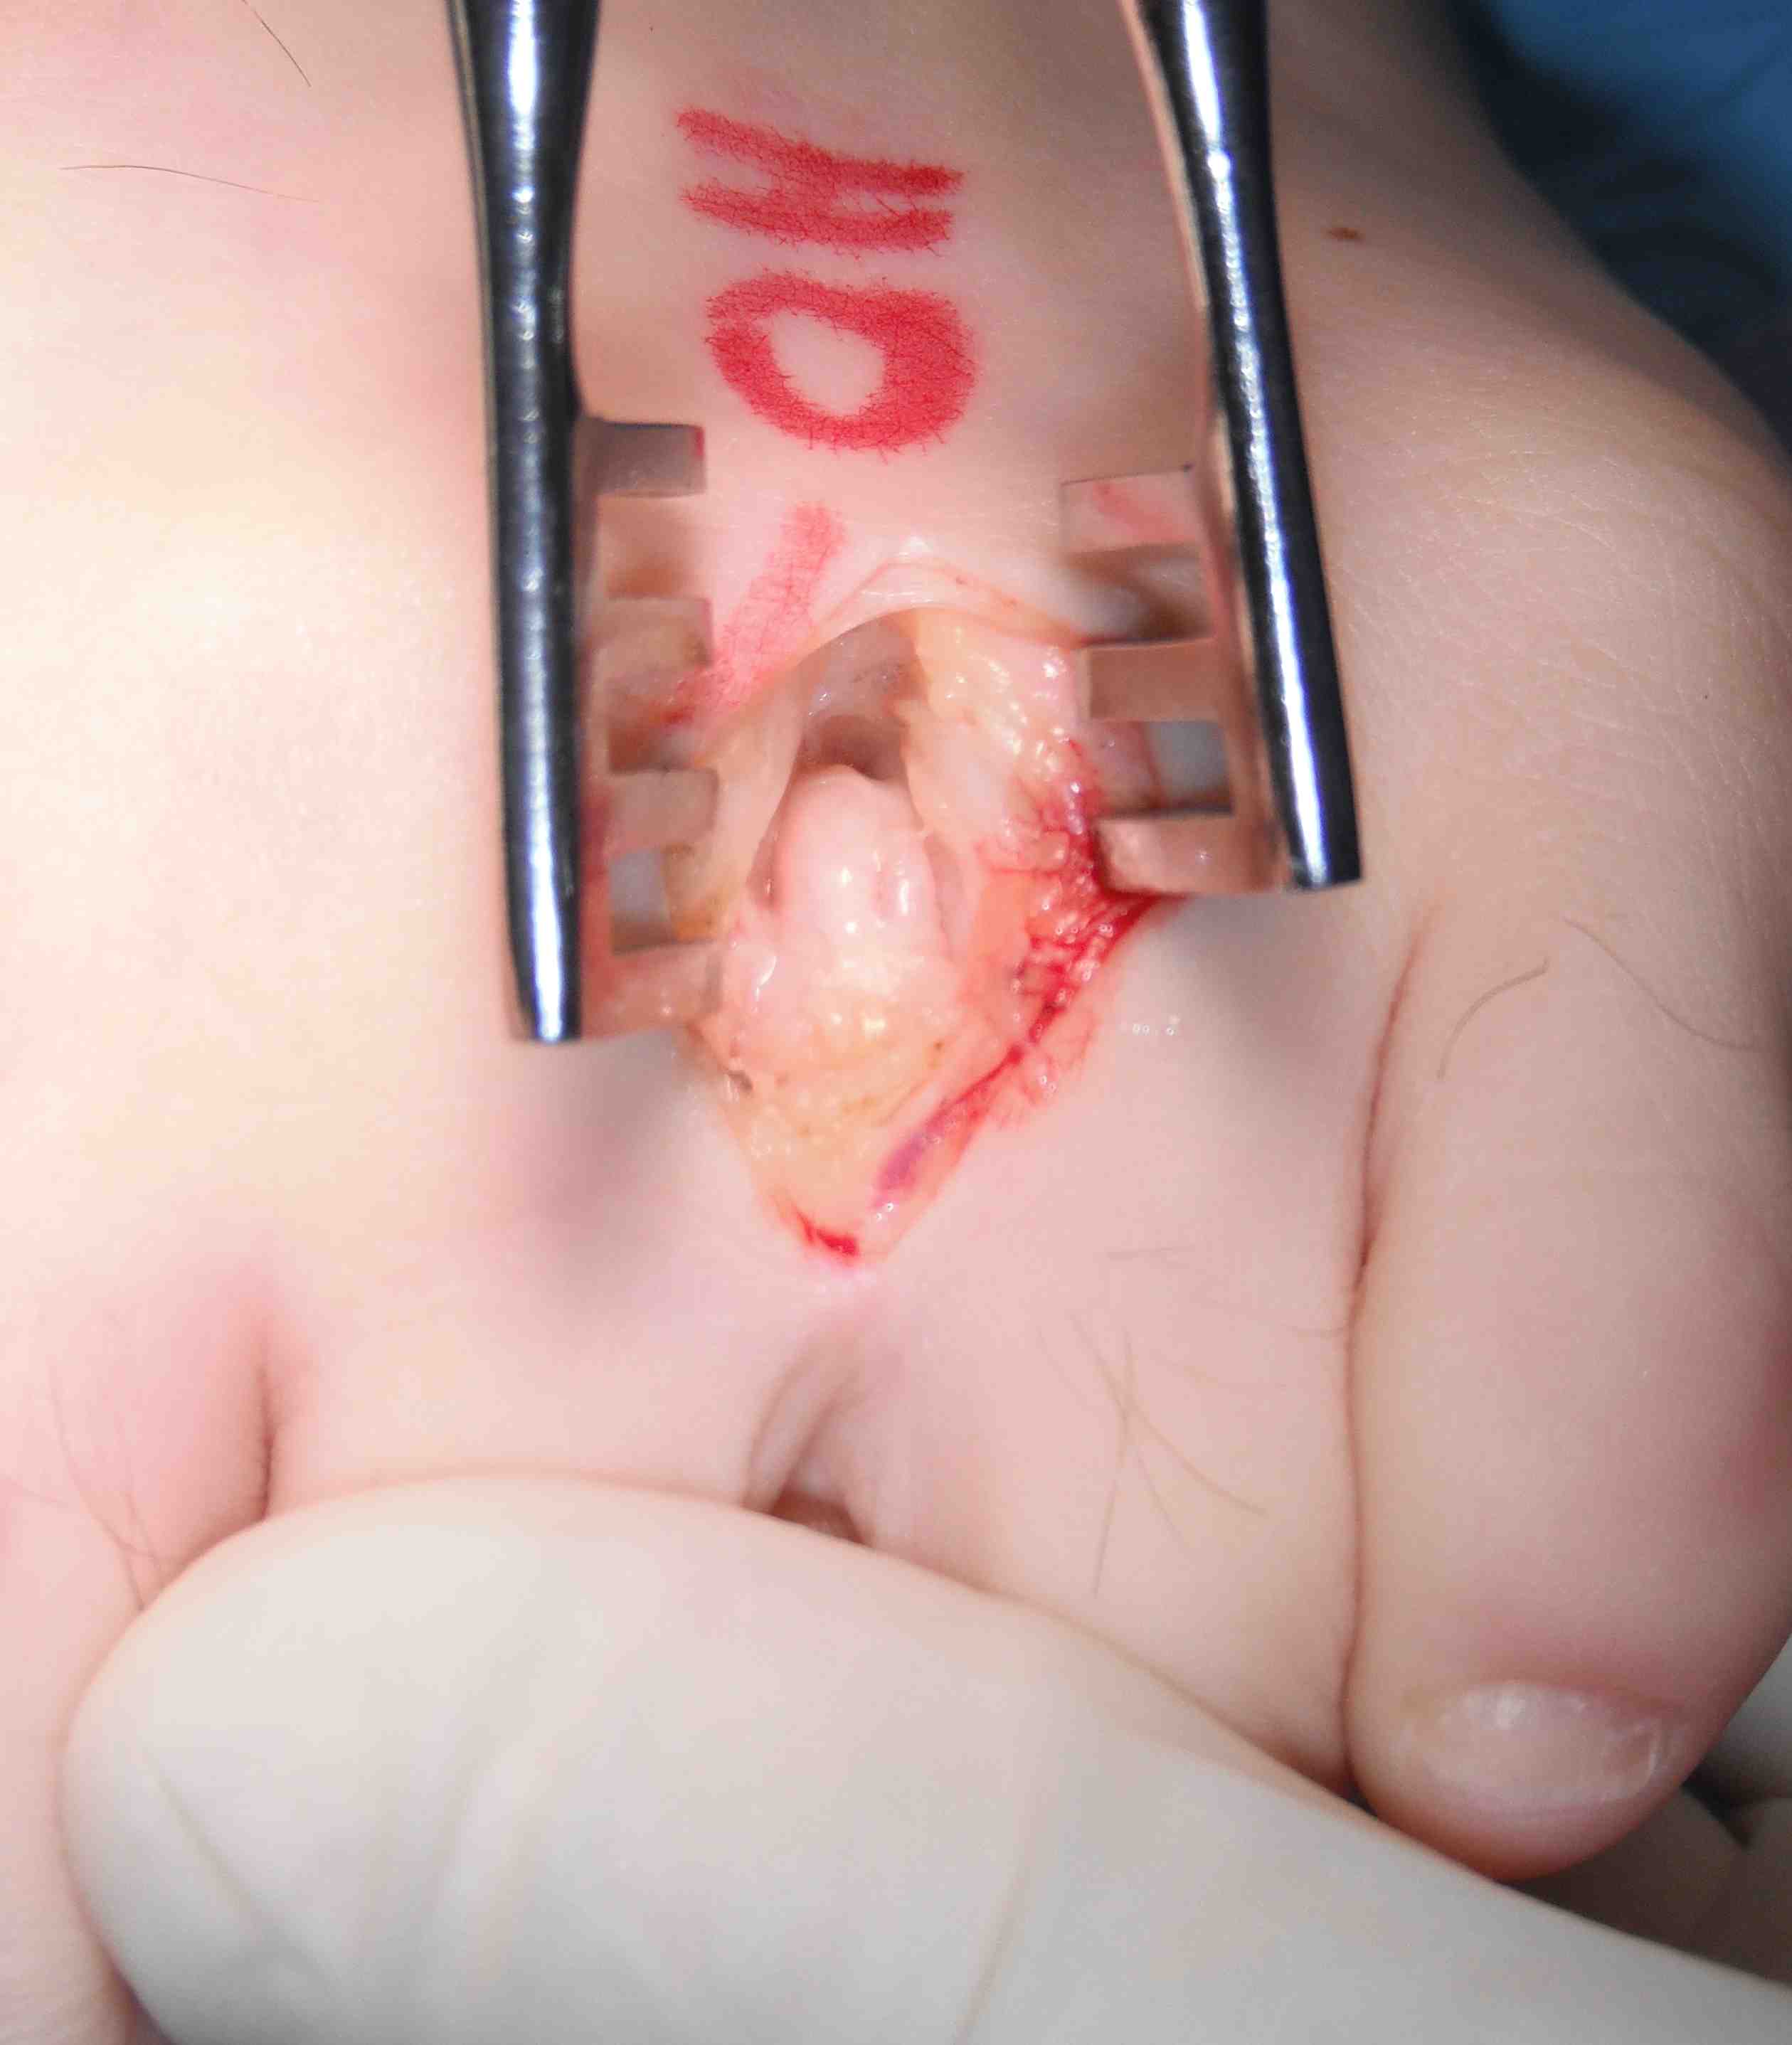

Resection Morton's neuroma

Technique

Vumedi Morton neuroma resection

Dorsal incision over the webspace

- separate metatarsals with lamina spreader / retractor

- divide deep metatarsal ligament

Identify common digital nerve proximally

- identify neuroma / place forceps under

- resect proximal to neuroma

- resect distal to bifurcation

Mortons Neuroma IncisionMortons Neuroma 1Mortons Neuroma 2

Mortons NeuromaMortons Neuroma